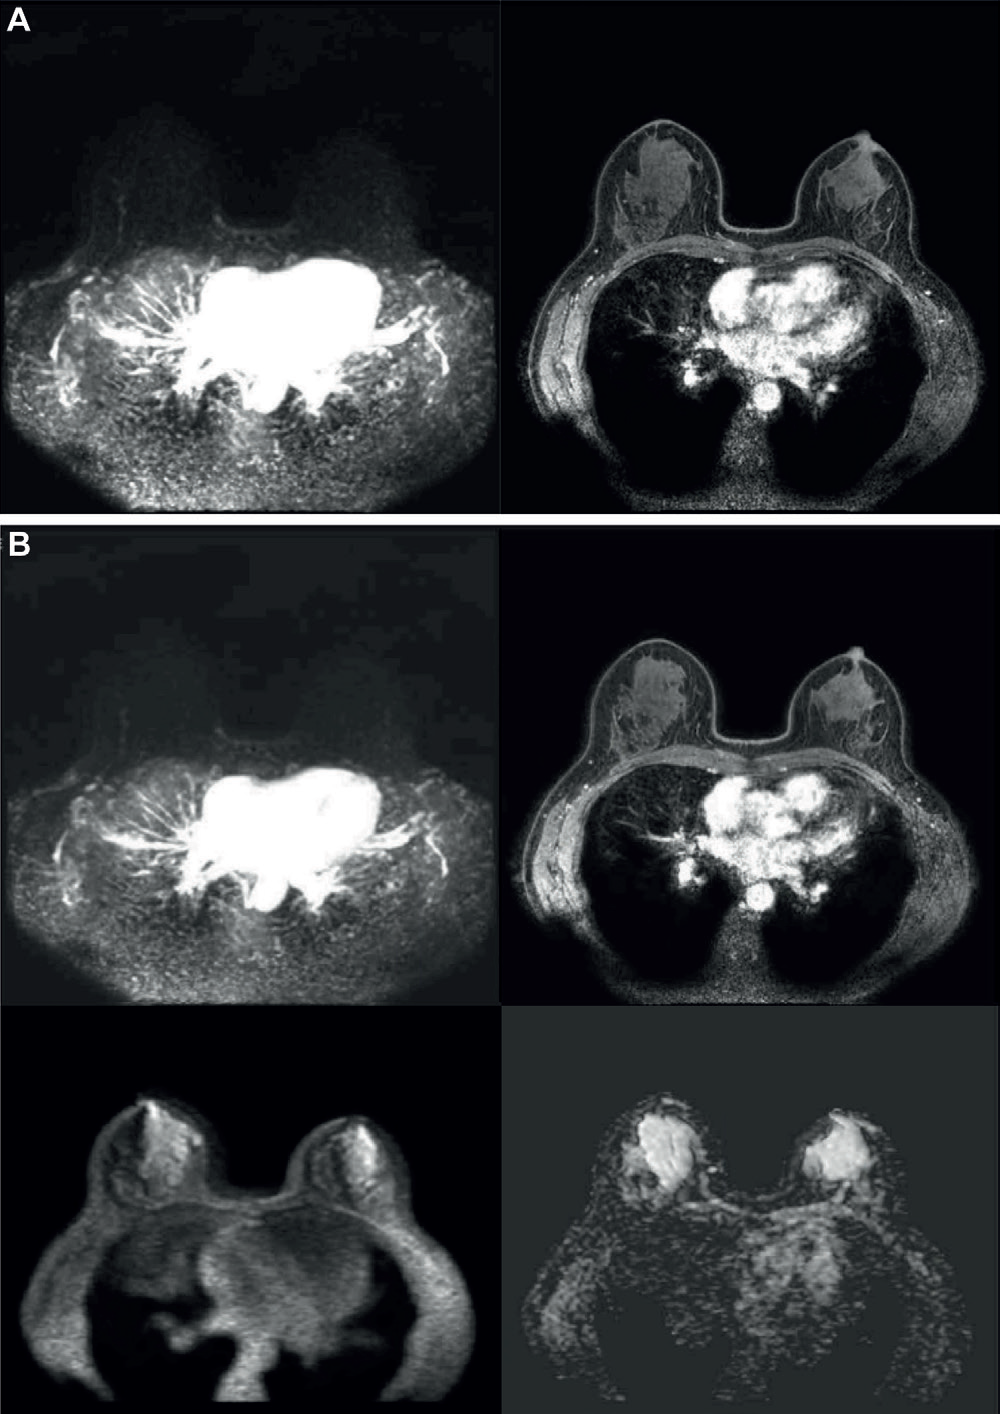

3. 临床价值:典型病例的极简协议表现

-

真阳性案例:6mm 不规则肿块,Step 1 显示早期快速强化(BI-RADS 4 类),活检证实浸润性癌。全参数序列(T2 低信号、DWI 受限、Type III 曲线)仅验证恶性,未改变召回决策。

-

假阳性案例:7mm 肿块 Step 1 误判为 BI-RADS 4 类,全参数序列同样支持恶性特征,但活检为硬化性腺病。提示极简协议的假阳性率与全参数相当。